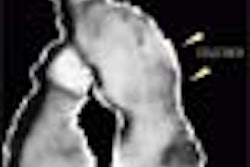

By adding MPS to IVUS, Boston Scientific and MediGuide hope to create IVUS systems that produce 3-D images. The company believes that such devices will provide more useful clinical information and allow for easier image interpretation than existing 2-D IVUS products.